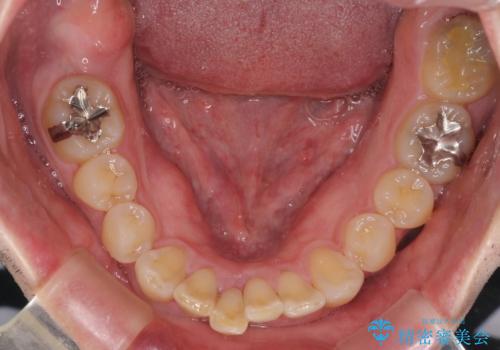

通常では速やかにオールセラミッククラウンにて補綴治療を行うのですが、デコボコしている歯列も気になっていたため、事前に矯正治療を行うこととしました。

上顎歯列の叢生が著しかったため、上顎左右第一小臼歯2本を抜歯し、目立たないワイヤー装置にて治療を進めることとしました。